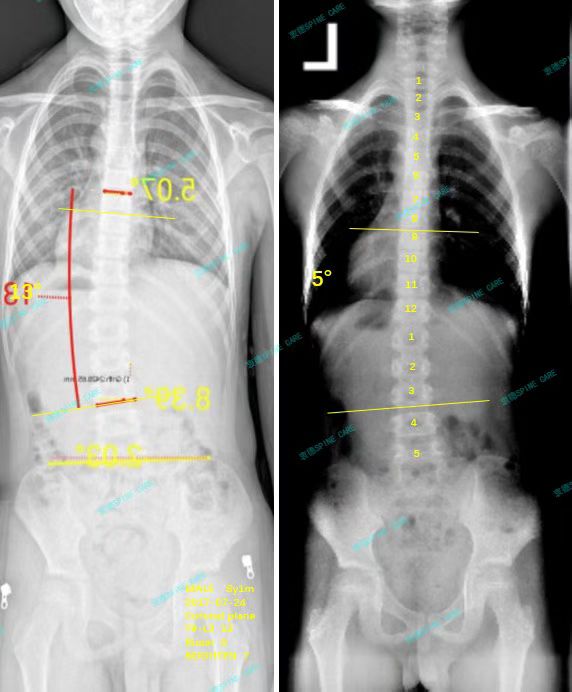

案例主人:夏天 发现侧弯年龄:8岁 侧弯情况:Cobb角度13度

在这里训练了三个月,我每天在家也坚持打卡训练。最近拍片一看,我的侧弯角度从13度降到了5度,我简直乐开了花!所有的努力都没有白费,我要特别感谢衷德脊柱的老师们,特别是杨博士,真的太感谢了!

After training here for three months, I also insist on checking in every day at home. When I took a recent photo shoot, my lateral bending angle dropped from 13 degrees to 5 degrees. I was so happy! All my efforts were not in vain. I would like to thank the teachers who are dedicated to their moral integrity, especially Dr. Yang. I am really grateful!